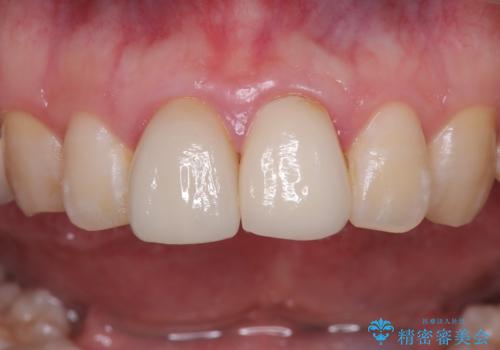

精密根管治療後、オールセラミッククラウンで治療を行いました。

治療後、違和感は無くなりました。

治療後、違和感が無くなり、被せ物で歯の長さが揃い見た目も改善されとてもご満足していただけました。